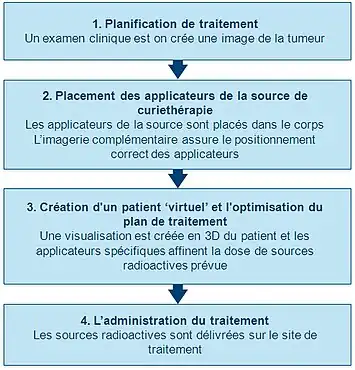

Planification initiale

Afin de planifier avec précision la procédure de curiethérapie, un examen clinique approfondi est effectuée afin de comprendre les caractéristiques de la tumeur. En outre, une gamme de modalités d'imagerie peut être utilisée pour visualiser la forme et la taille de la tumeur et sa relation avec les tissus environnants et les organes. Il s'agit notamment de la radiographie, de l'échographie, de la tomographie axiale par ordinateur (CT ou CAT) et de l'analyse et l'imagerie par résonance magnétique (IRM). Les données de plusieurs de ces sources peuvent être utilisées pour créer une visualisation 3D de la tumeur et des tissus environnants.

En utilisant cette information, un plan de la répartition optimale des sources de rayonnement peut être développé : les supports de sources (instruments), qui sont utilisés pour apporter le rayonnement au site de traitement sont placés et positionnés. Les applicateurs qui sont non radioactifs et sont généralement des aiguilles ou cathéters en plastique. Le type spécifique de l'applicateur utilisé dépendra du type de cancer traité et des caractéristiques de la tumeur cible. Cette planification initiale permet de garantir que les « points froids » (trop peu irradiés) et des « points chauds » (trop irradiés) sont évités pendant le traitement. Ils pourraient se traduire respectivement par l'échec du traitement ou des effets secondaires.

Imagerie et insertion de l'applicateur

Avant que les sources radioactives ne soient délivrées sur le site de la tumeur, les applicateurs doivent être insérés et positionnés correctement en fonction du planning initial.

Les techniques d'imagerie, telles que les rayons X, la fluoroscopie et l'échographie sont généralement utilisées pour aider au placement des applicateurs sur leurs positions exactes et de pour affiner le plan de traitement. Les scans CAT et l'IRM peuvent aussi être utilisés. Une fois que les applicateurs sont insérés, ils sont maintenus contre la peau en utilisant des sutures ou du ruban adhésif pour les empêcher de se déplacer. Une fois que les applicateurs sont bien positionnés, l'imagerie complémentaire peut être réalisée pour orienter la planification du traitement détaillé.

Création d'un patient virtuel

Les images du patient portant les applicateurs in situ sont importées dans un logiciel de planification du traitement. Le patient est alors amené dans une salle spéciale et blindée pour le traitement. Le logiciel de planification du traitement permet l'acquisition de multiples images 2D du site de traitement. Ces images sont traduites en un « patient virtuel » 3D, dans lequel la position des applicateurs peuvent être définis. Les relations spatiales entre les applicateurs, le site de traitement et les tissus environnants sains sont dans ce « patient virtuel », une copie des relations dans le patient réel.

Optimisation du plan d'irradiation

Pour identifier la optimale répartition spatiale et temporelle des sources de rayonnement dans les applicateurs sur ses cibles, le logiciel de planification du traitement place dans un premier temps les sources de rayonnement virtuelles à l'intérieur du patient virtuel. Le logiciel montre une représentation graphique de la distribution de l'irradiation. Cette étape sert de guide à l'équipe de curiethérapie pour affiner la répartition des sources et de fournir un plan de traitement qui est parfaitement adaptée à l'anatomie de chaque patient. Ensuite, la radiation du patient réel peut commencer. Cette approche est parfois appelée « peinture de la dose ».